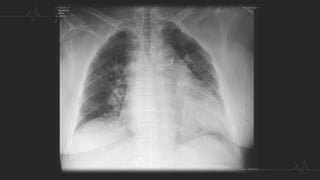

HALLAZGOS RADIOGRÁFICOS

RADIOGRAFÍA DE TORAX

 Ensanchamiento de la silueta cardiomediastínica, debido al aumento del

calibre de las arterias centrales.

 Infarto pulmonar. Se observa un infiltrado alveolar localizado , en forma de

cuña, triangular y de base pleural, generalmente basal, con borde inferior

convexo (joroba de Hampton)

 Signos de Wetsermark: área de enfisema local causado por un defecto

en la perfusión que con leva una hiperclaridad marcada.

 Signo de Fleischner: dilatación de la arteria debido a la impactación del

émbolo.

 Atelectasias laminares basales con elevación del hemidiafragma

 Derrame pleural

Joroba de Hampton Signo de Fleischner

Signo de Westermark

RADIOGRAFÍA DE TORAX Ensanchamiento de la silueta cardiomediastínica, debido al aumento del calibre de las arterias centrales.  Infarto pulmonar. Se observa un infiltrado alveolar localizado , en forma de cuña, triangular y de base pleural, generalmente basal, con borde inferior convexo (joroba de Hampton)  Signos de Wetsermark: área de enfisema local causado por un defecto en la perfusión que con leva una hiperclaridad marcada.  Signo de Fleischner: dilatación de la arteria debido a la impactación del émbolo.  Atelectasias laminares basales con elevación del hemidiafragma  Derrame pleural

Joroba de HamptonSigno de Fleischner